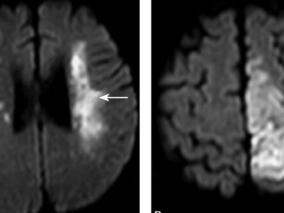

1小时条评论1 病例简介 患者女,76岁,退休工人,因反复头昏脑涨、胸闷心慌、血压不稳定5个月于2011年10月31日就诊。 患者曾因左上肢无力、麻木10天于2011年5月30日以脑梗死住我科,住院期间,经头颅MRI及脑血管造影检查诊断为右侧放射冠脑梗死,右大脑中动脉M1段狭窄,于2011...